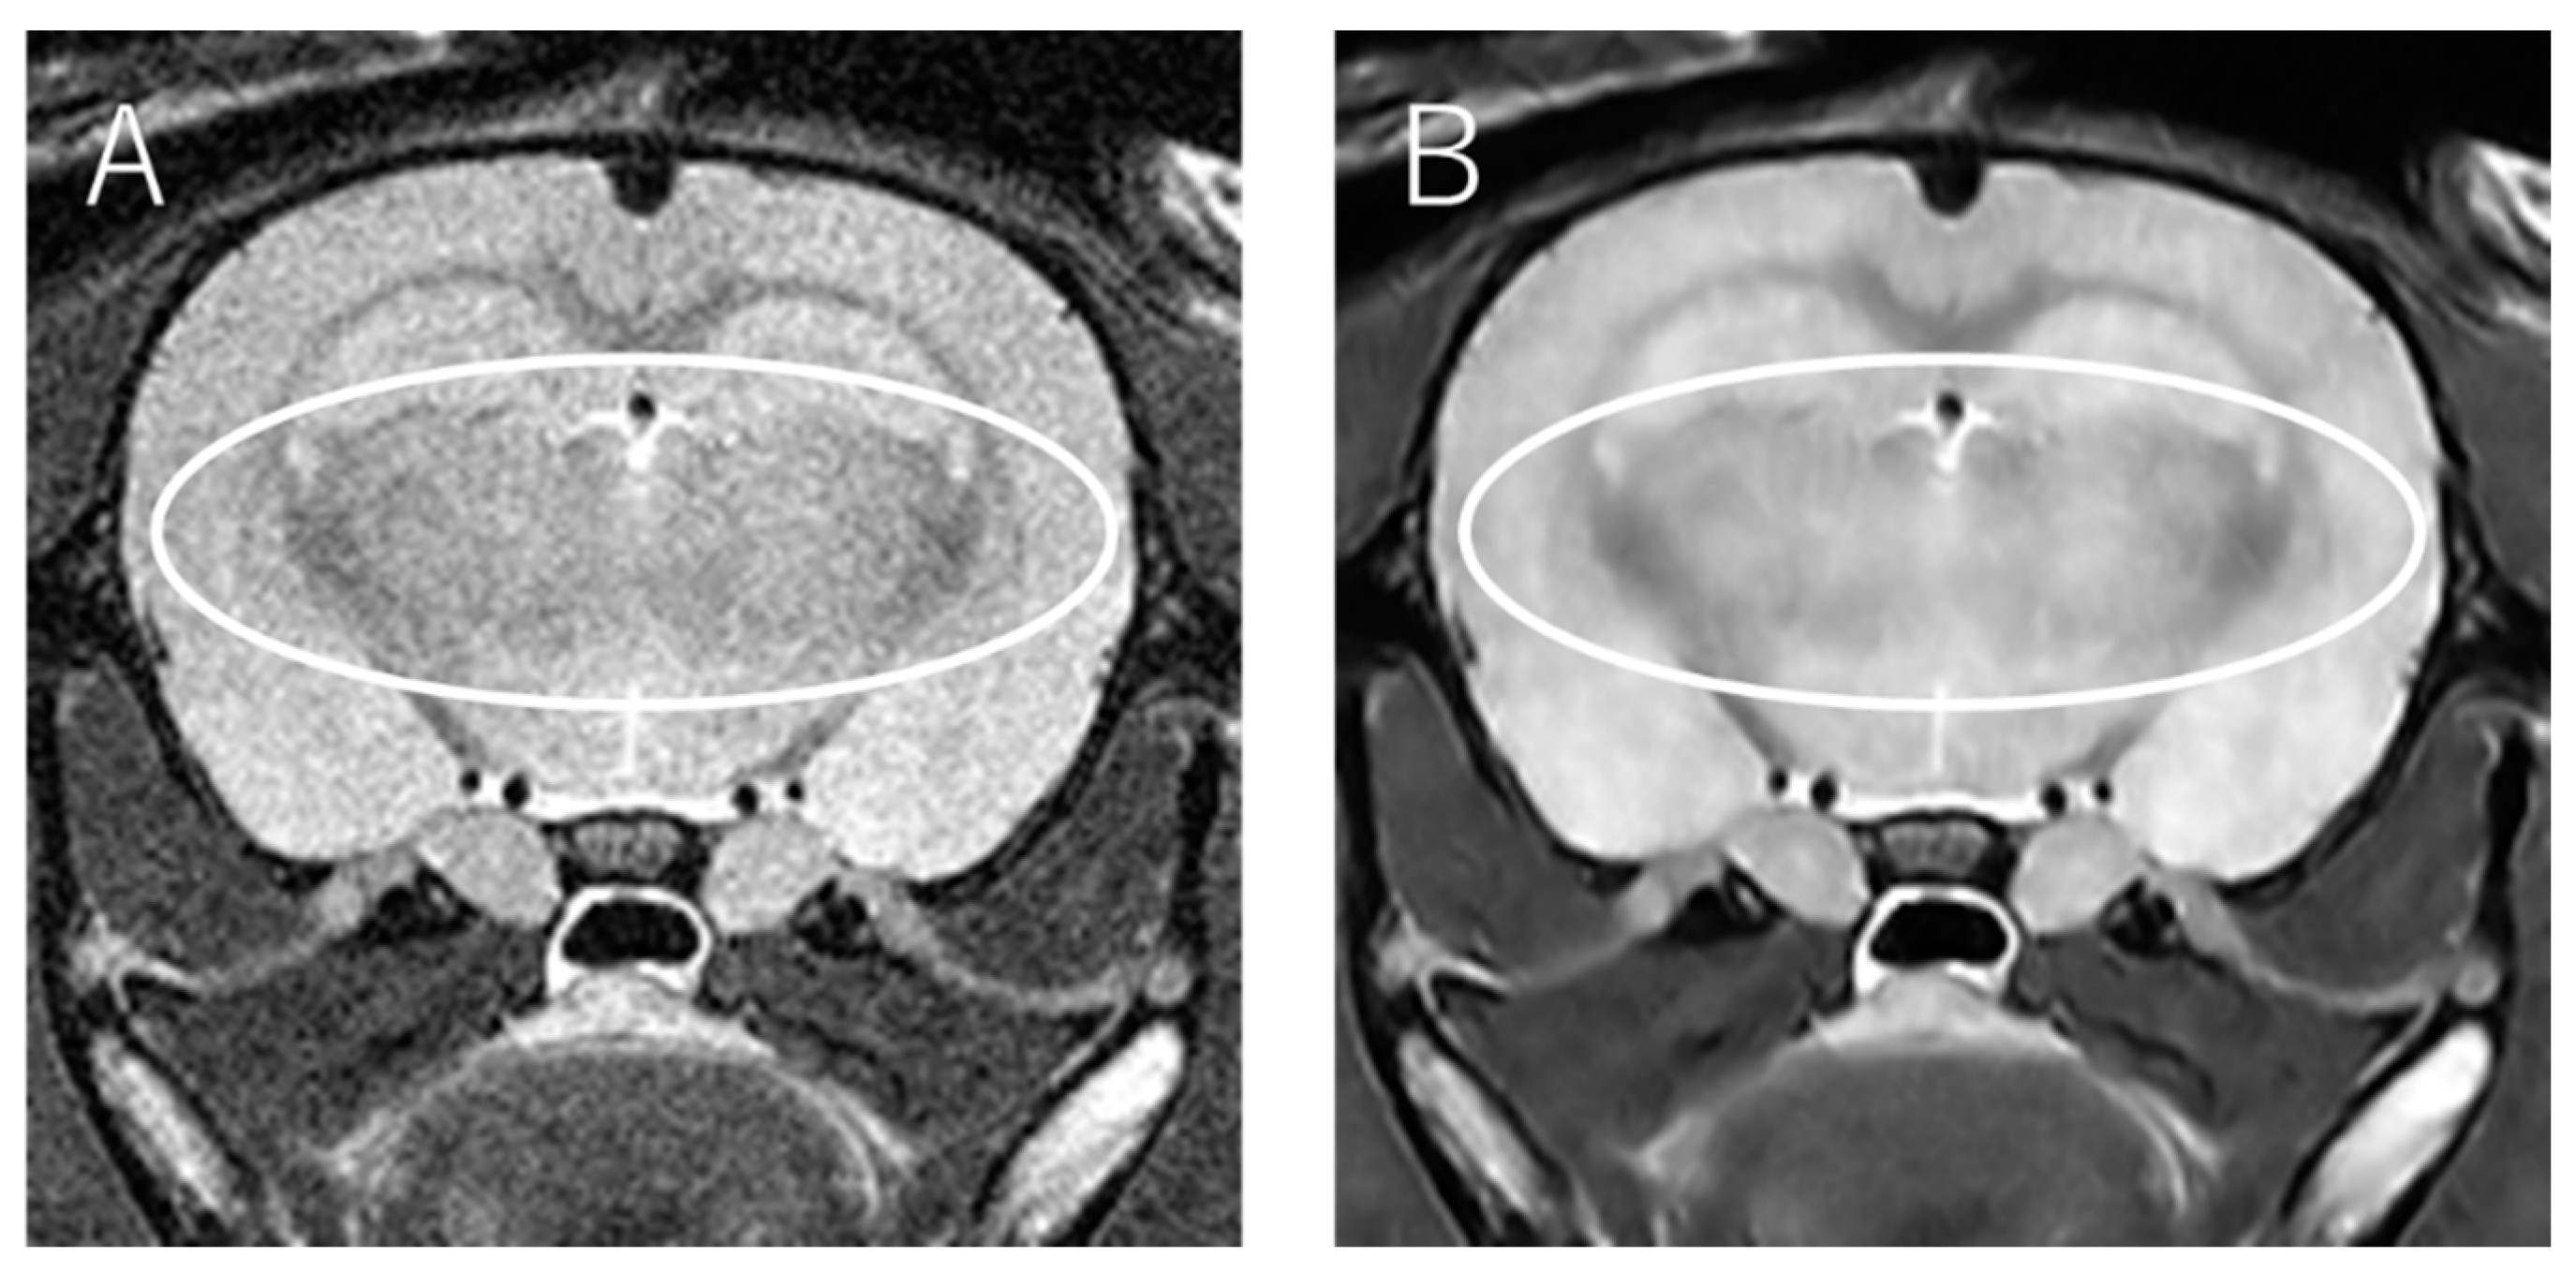

The presence of artifacts in the input image was reflected in the reconstructed image (Figure 5).

NEX2 input image (A) and its reconstructed image (B). The artifacts in the area surrounded by white lines are also reflected in the reconstructed image. NEX, number of excitations.

In a study by Kidoh et al. [3], deep learning-based reconstruction of brain MRI images (3T) of five people with different added noises was conducted, and the PSNR and SSIM were measured as quantitative evaluations. DnCNN and SCNN were used as network comparators, and both the PSNR and SSIM values were higher for deep learning-based reconstruction than for DnCNN and SCNN. In the present study, the use of RDN significantly increased the PSNR at NEX2 and the SSIM at NEX2 and NEX4, which is consistent with previous studies. We consider that RDN could be one of the methods used to improve the image quality in 7T MRI. Meanwhile, in this study, the presence of artifacts in the input image was reflected in the reconstructed image. This is thought to be due to the fact that the learning model performed noise reduction while retaining the artifacts. Therefore, in the network used in this study, the quality of the input image was guaranteed to some extent.